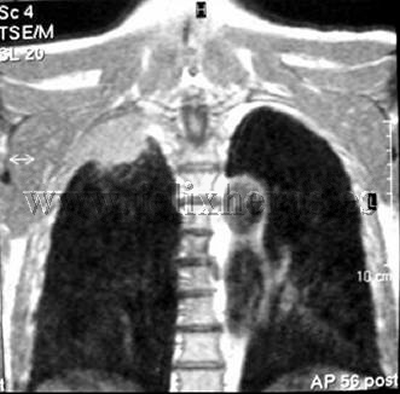

Cáncer de pulmón